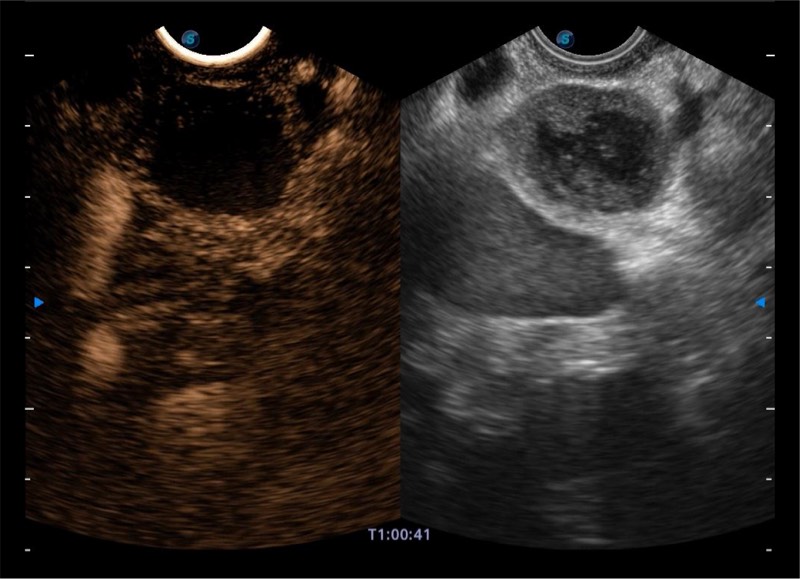

搭载百万级CMOS成像技术

及自主研发凸阵换能器,

可呈现优质的内镜和超声画面

基于二十年的超声技术积累,百老汇电子游戏官网提供了最新一代的独立超声主机,在提供高质量图像的同时满足多学科使用。具备常见多普勒技术并提供弹性成像、声学造影等高端影像技术。新一代传感器具有更强的抗干扰能力并减少图像伪影。

4-12MHZ宽频输出